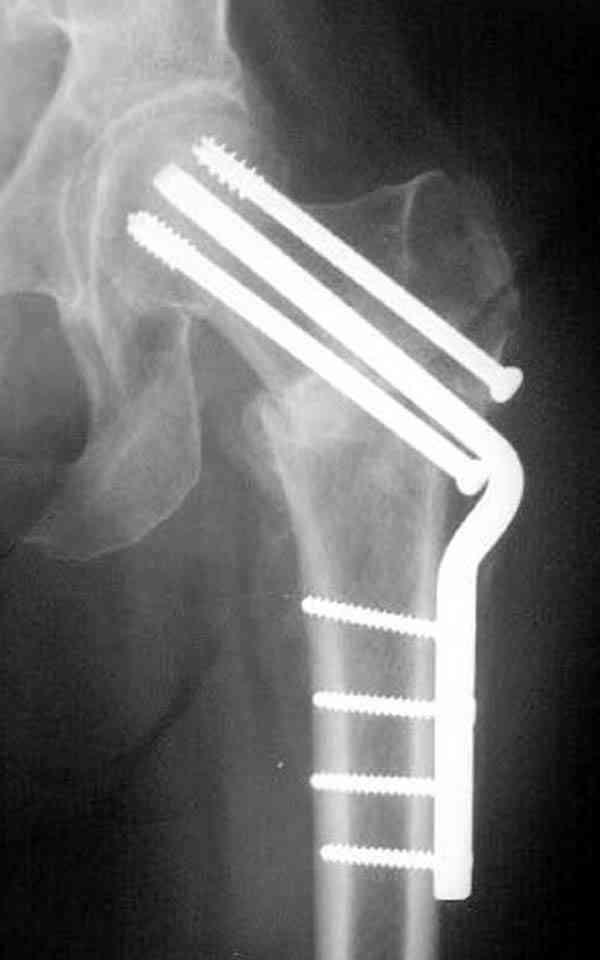

Здесь случай перелома из-за ослабления латерального кортекса через 3 недели после операции на шейке. Шурупы были установлены под большим углом, слабый латеральный кортекс не выдержал нагрузку.

Кстати, очень сомнительна остеопорозность на правом оперированном бедре, отсутствует данные денситометрии с индексом остеопороза.

Коллега Челноков прав, здесь еще имеется риск перелома за счет ослабления латерального кортекса. Во время установки канюлированных шурупов за редким исключением спица вводится с одного раза, множественные попытки ослабляют латеральный кортекс, что станет источником перелома в этом месте.

В идеале для профилактики рефрактуры шурупы надо вводить не больше, чем под 130 градусным углом и не ниже уровня малого вертела.

Насчет биомеханических преимуществ одного шурупа тоже возникает вопрос. Если придерживаться канонов механики, для перелома шейки необходимо 3 паралельных шурупа, расположенных ближе к кортикальному слою шейки.